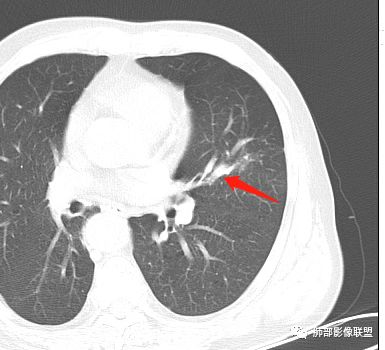

临床特点老年男性、有咯血一个月

影像学特点:肺气肿背景下在大概一年的时间里出现了一个光滑的小结节,因为图像给的不是太薄,与支气管的关系判断不清,从结节周围出现斑片状炎症来判断,应该考虑结节位于支气管内,周围是阻塞性炎症,这样比较容易解释咯血

纵隔窗上似乎结节内可见点状高密度影,同时没有明显肿大淋巴结

所以我考虑支气管内的恶性肿瘤,类癌可能大。

左肺上叶小结节病灶,形态规则,边缘光滑,密度至密,远处阻塞性肺炎,病灶与支气管关系密切,给图太少不好观察,考虑神经内分泌癌(类癌),其次鳞癌

左肺上叶光滑结节影 似乎与支气管没有关系  ,给的纵隔窗病灶中心似乎点状钙化  病灶旁有更小结节,与上一年片比较 结节增大明显  考虑恶性 类癌可能

老年男性,肺气肿基础。约一年时间出现左肺上叶舌段支气管近端结节影,远端斑片样阴影,边缘模糊。考虑近端恶性占位,远端有阻塞性炎症。

左肺上叶舌段支气管管壁略增厚 间隔一年 管壁增厚明显 向腔外突出形成结节 管腔闭塞 远端片状及斑片影 纵隔淋巴结增大 肺气肿背景 考虑鳞癌伴阻塞性炎症可能

前次片2016年4月20相应位置就有小点状病灶,2017-5-15呈结节影改变,边界膨隆,远端阻塞炎性改变,考虑肺癌,鉴别炎性结节!